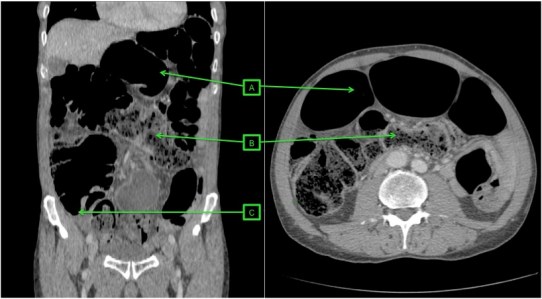

La imagen de TC del mismo paciente nos permite confirmar este hallazgo. A la derecha, imagen coronal. A la izquierda, imagen axial. A: sigma volvulado. B: colon transverso lleno de heces. C: ciego.